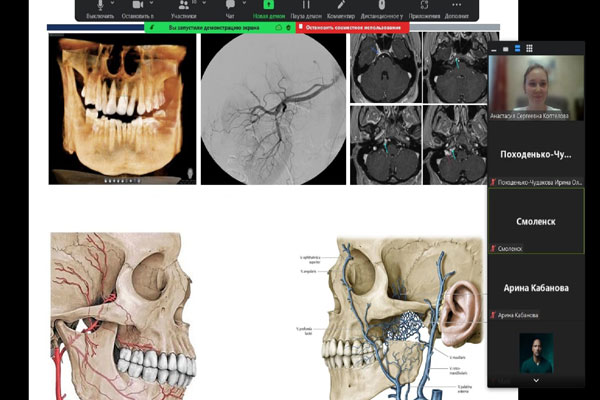

ВОЗМОЖНЫЕ СТОМАТОЛОГИЧЕСКИЕ ПОСЛЕДСТВИЯ КОВИДА